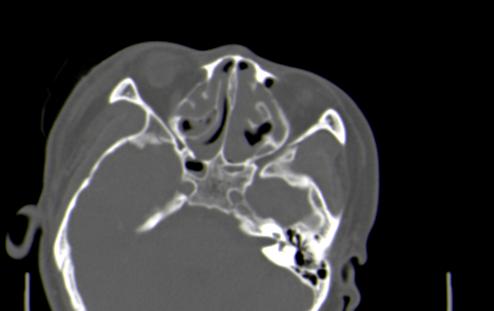

以下是引用皎皎白驹在2006-11-29 8:48:00的发言:[br]影像表现:双侧筛窦和上颌窦、鼻腔内均密度增高,右侧视神经增粗、弯曲,左筛窦顶部筛板及右侧纸板近视神经孔区可见骨折线。[br]结合临床表现考虑:右侧筛窦纸板近视神经孔区骨折致右侧视神经损伤。最好做个眼眶冠状扫描,更明确右侧视神经管是否狭窄。

以下是引用w_jianhua在2006-11-29 10:07:00的发言:[br]影像表现:双侧筛窦和上颌窦、鼻腔内均密度增高,右侧视神经增粗、弯曲,左筛窦顶部筛板及右侧纸板近视神经孔区可见骨折线。[br]结合临床表现考虑:右侧筛窦纸板近视神经孔区骨折致右侧视神经损伤。最好做个眼眶冠状扫描,更明确右侧视神经管是否狭窄。 [br] [br]支持[br]

以下是引用守望可可西里在2006-11-29 9:46:00的发言:[br][quote]以下是引用皎皎白驹在2006-11-29 8:48:00的发言:[br]影像表现:双侧筛窦和上颌窦、鼻腔内均密度增高,右侧视神经增粗、弯曲,左筛窦顶部筛板及右侧纸板近视神经孔区可见骨折线。[br]结合临床表现考虑:右侧筛窦纸板近视神经孔区骨折致右侧视神经损伤。最好做个眼眶冠状扫描,更明确右侧视神经管是否狭窄。